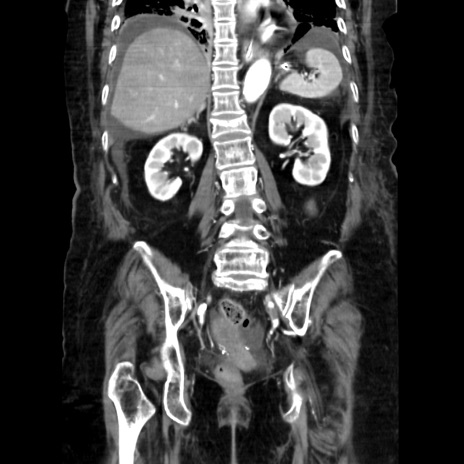

症例40(冠状断像)

【症例】90歳代女性

【主訴】腹痛・嘔吐

【現病歴】 食欲低下、嘔吐があり昨日他院受診。肺炎と診断され入院となる。入院後より腹部全体に圧痛あり。胃管留置され経過みていたが、症状持続するため、

当院転院となる。

【既往歴】胸椎圧迫骨折、胆石症

【身体所見】腹部:中央に激痛あり、圧痛あり、反跳痛不明

【データ】WBC 17100、CRP 18.82

冠状断像